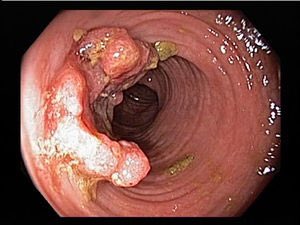

عادةً يتطور السرطان من لحميات(سلائل)في القولون وهي تجمعات من الخلايا الحميدة لا تسبب اي اعراض ظاهرة في اغلب الاوقات.مع مرور الزمن تتحول هذة اللحميات اللي خلايا ما قبل سرطانية ثم سرطانية ينشأ منها سرطان القولون. تحول السلائل الى سرطانات يستغرق وقت طويل من الزمن قد يمتد الى ١٠سنوات

قد تتكون هذة السلائل من طفرات جينية ولكن هذا ليس شائعاً إطلاقاً ومن الاعراض التي قد تسببها دم ظاهر او خفي(يتم الكشف عنه من فحص البراز) او افرازات مخاطية مصاحبة للبراز. يتم الكشف عن هذة السلائل بالمنظار السفلي وازالتها في وقت الكشف قبل ان تتطور الى خلايا سرطانية بدون عمليات جراحية